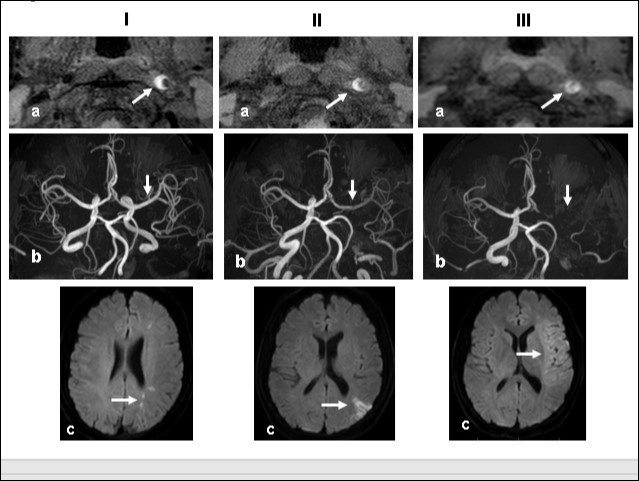

Figure 2.Time course Columns I, II, and III are images obtained 1, 2, and 3 weeks, respectively, after the start of dissection of the cervical segment of the internal carotid artery. Ia, IIa, IIIa.T1 VISTA images of the same segment shown in Fig. 1C. The dark area reflective of the low void progresses to hyperintensity by week 3. IIIa shows complete occlusion of the true lumen by the intramural hematoma (arrow ). Ib, IIb, IIIb. TOF-MRA images of the intracranial arteries. (a) The left MCA is supplied via antegrade flow from the left carotid artery (arrow). (b) Flow from the left carotid artery disappeared from the ICA bifurcation to the top of the ICA. Blood supply to the left MCA derives from the circle of Willis via the anterior- or the posterior communicating artery (arrows). By week 3, flow to the left MCA, even via the left A1 segment of the anterior cerebral artery had disappeared completely. Ic, IIc, IIIc. Diffusion-weighted images at the basal ganglia level. Week 1: a few hyperintense areas are visualized in the border zone of the left cerebrum (arrow). Week 2: Note the hyperintensity area in the watershed zone between the left ACA and the MCA, and between he MCA and the PCA (arrow). The image acquired on week 3 shows a diffuse hyperintensity area in the left MCA territory (arrow).

Time course Columns I, II, and III are images obtained 1, 2, and 3 weeks, respectively, after the start of dissection of the cervical segment of the internal carotid artery. Ia, IIa, IIIa.T1 VISTA images of the same segment shown in Fig. 1C. The dark area reflective of the low void progresses to hyperintensity by week 3. IIIa shows complete occlusion of the true lumen by the intramural hematoma (arrow ). Ib, IIb, IIIb.  TOF-MRA images of the intracranial arteries. (a) The left MCA is supplied via antegrade flow from the left carotid artery (arrow). (b) Flow from the left carotid artery disappeared from the ICA bifurcation to the top of the ICA. Blood supply to the left MCA derives from the circle of Willis via the anterior- or the posterior communicating artery (arrows). By week 3, flow to the left MCA, even via the left A1 segment of the anterior cerebral artery had disappeared completely. Ic, IIc, IIIc.  Diffusion-weighted images at the basal ganglia level. Week 1: a few hyperintense areas are visualized in the border zone of the left cerebrum (arrow). Week 2: Note the hyperintensity area in the watershed zone between the left ACA and the MCA, and between he MCA and the PCA (arrow). The image acquired on week 3 shows a diffuse hyperintensity area in the left MCA territory (arrow).

This 43-year-old Japanese male presented with right hand dysesthesia. He has not recognized his neck pain and Horner’s syndrome( oculosympathetic palsy). Magnetic resonance imaging(MRI) performed on a 3T TX scanner (Philips Achieva, The Netherlands) demonstrated dissection of the left cervical carotid artery (CCA; Figure 1A,1B ); no ischemic area was detected in the left cerebral brain. Axial section views of the CCA segment revealed a typical crescent hematoma; a bright, hyper-intense circle representing the narrowed arterial lumen was visualized. A T1-volumetric isotropic turbo spin echo acquisition (VISTA) sequence resulted in the diagnosis of dissection of the CS-ICA (Figure 1C). He had no conventional stroke risk factors such as hypertension, diabetes, hyperlipidemia, a history of cardiac valvular disease, arterial fibrillation, or features of inherited connective tissue disorder. Also absent was a history of arterial trauma and we were unable to identify any etiological factor(s). One week later he developed Gerstman symptoms; border zone ischemia was observed in the left cerebrum (Figure 2-Ic). He was admitted and the administration of antiplatelet agents was started. The left middle cerebral artery (MCA) was supplied via antegrade circulation (Figure 2-Ib) and an increase in the flow-void intensity was noted (compare Figure 1C with Figure 2-Ia). MRI studies acquired one week later revealed spreading of the ischemic area to beyond the watershed zone between the left anterior cerebral artery (ACA) and the MCA, and the MCA and the posterior cerebral artery (PCA) (Figure 2-IIc). The area of dissection had spread from the ICA bifurcation to the top of the ICA. The blood supply to the left MCA territory derived from the circle of Willis (Figure 2-IIb). The flow-void intensity had increased further (compare Figure 2-Ia with Figure 2-IIa). Two weeks after his admission he suddenly experienced complete right-sided hemiparesis with motor aphasia. MRI performed within 45 min demonstrated diffuse ischemia in the left MCA territory (Figure 2-IIIc), the left A1 segment could not be visualized. The left MCA and its A1 segment were completely occluded (Figure 2- IIIb). The flow-void intensity indicated complete occlusion of the true lumen (Figure 2-IIIa). He underwent emergency left superficial temporal artery (STA)-MCA bypass surgery within 6 hours; double anastomosis was successful. External decompression was performed to prevent neurological deterioration due to severe brain swelling. An intensive rehabilitation has been continued for him after operation. His functional independence measure (FIM) score recorded over the course of 4 months showed remarkable improvement ( Figure 3) as did the standard language test for aphasia.